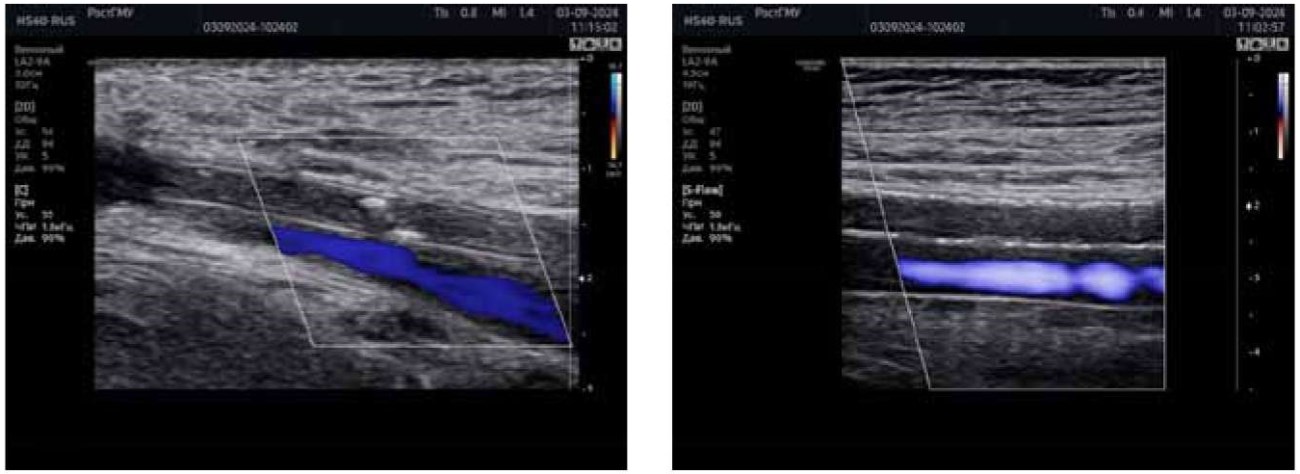

При ультразвуковом исследовании отмечена проходимость подвздошных, общих бедренных, глубоких, поверхностных бедренных подколенных артерий с обеих сторон, окклюзия артерий голени и тыла стопы справа (рис. 1 (а, б)).

Рисунок 1 (а, б). Фотография ультразвукового исследования артерий правой нижней конечности пациента У., 56 лет. А — признаки окклюзии задней большеберцовой артерии. Б — признаки окклюзии передней большеберцовой артерии. (изображение авторов)

Figure 1 (a, b). Ultrasound image of the arteries of the right lower limb of patient U., 56 years old. A — signs of posterior tibial artery occlusion. B — signs of anterior tibial artery occlusion. (Photograph of the authors)